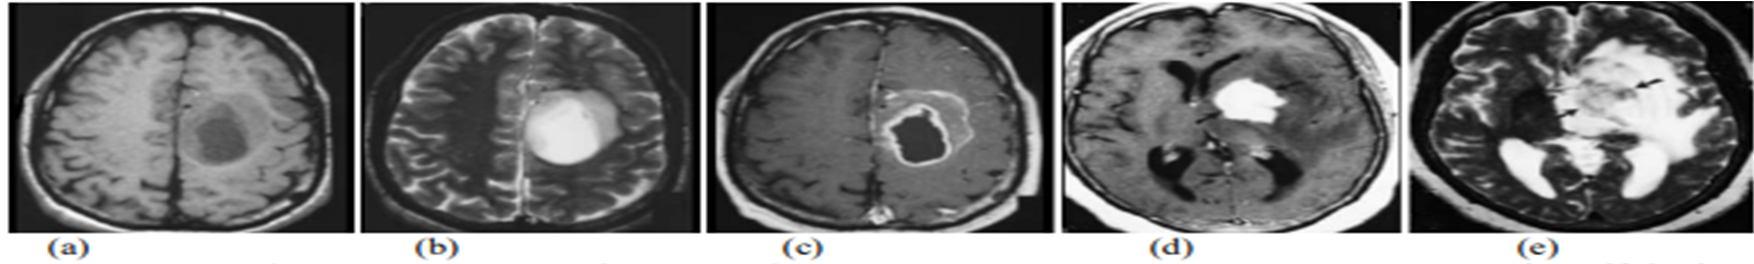

Figure 2 : MRI of brain cited by http://www.mr-tip.com/serv1.php?type=isimg. T2 weighted MR image (a) brain shows cortex, lateral ventricle, and falx cerebri, (b) brain shows eyeballs with optic nerve, medulla, vermis, and temporal lobes with hippocampal regions, (c) head shows maxillary sinus, nasal septum, clivus, inner ear, medulla, and cerebellum. T1 weighted MR image (d) brain shows cortex, white and grey matter, third and lateral venticles, putamen, frontal sinus and superior sagittal sinus, (e) brain shows eyeballs with optic nerve, medulla, vermis, and temporal lobes with hippocampal regions,(f) brain shows cortex with white and grey matter, corpus callosum, lateral ventricle, thalamus, pons and cerebellum from the same patients Most Research in developed countries show that the number of people who develop brain tumors and die from them has increased perhaps as much as 300 over past three decades. The National Brain Tumor Foundation (NBTF) for research in United States estimates that 29,000 people in the U.S are diagnosed with primary brain tumors each year, and nearly 13,000 people die. In children, brain tumors are the cause of one quarter of all cancer deaths. In India, totally 80,271 people are affected by various types of tumor (2007 estimates).